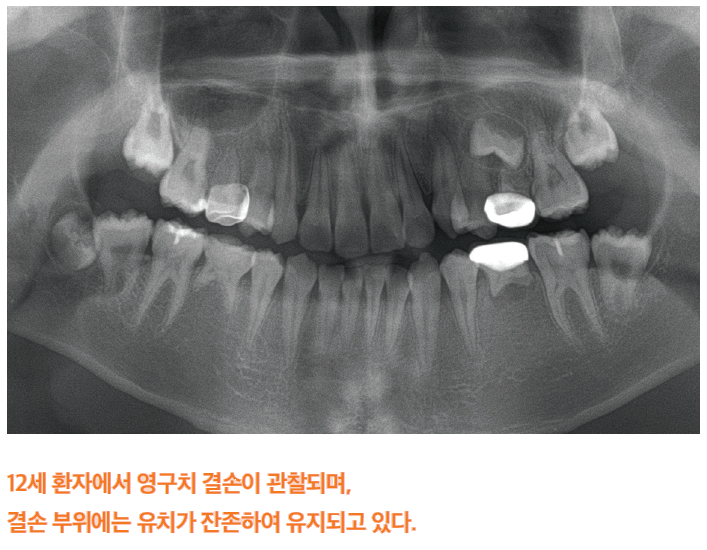

선천성 결손치란 태어날 때부터 영구치가 하나 이상 없는 상태를 의미하며, 사랑니(제3대구치)를 제외한 정상적인 28개의 영구치 가운데 일부 치아가 결손된 경우를 말합니다. 이는 치아의 발생 과정 중 치배 형성에 문제가 생겨 발생하게 됩니다. 결손된 치아의 수에 따라 일부 치아가 결손된 경우를 부분무치증(hypodontia), 6개 이상의 치아가 결손된 경우를 oligodontia, 그리고 모든 치아가 결손된 경우를 완전무치증(anodontia)으로 분류합니다. 이 중 oligodontia와 완전무치증은 비교적 드물게 나타납니다.

선천성 결손치의 치료는 환자의 나이, 결손 부위와 수, 잔존 치아의 상태, 안모 형태, 경제적 여건 등을 종합적으로 고려하여 개별화된 치료 계획을 세우는 것이 필요합니다.

공간 유지 후 보철 수복 - 성장이 완료된 후 시행하는 것이 원칙입니다. 성장기에서는 가철식 공간유지장치나 가철식 의치 등을 사용하여 공간을 유지하고, 성장 완료 후 고정성 보철물이나 임플란트 수복을 시행합니다. 이 경우 치아의 배열을 위한 교정치료가 선행되는 경우도 있습니다.